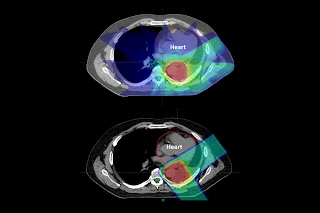

綠色:質子 紅色:重粒子 藍色 傳統光子

上方:傳統光子 下方:質子治療 減少心臟輻射傷害 (中國醫)